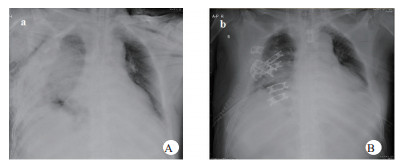

1 资料与方法患者,男,63岁,因“车祸致呼吸困难1 d”入院。既往体健。患者于2019年9月30日翻车致胸部挤压性创伤,伤后出现极度呼吸困难,送至当地医院,测血压80/50 mmHg(1 mmHg=0.133 kPa),胸部CT提示右侧血气胸,给予输血补液、去甲肾上腺素维持血压,经鼻气管插管呼吸机辅助通气,放置胸腔闭式引流管2根。因循环及氧合维持困难,10月1日转至徐州医科大学附属医院,收入EICU。入院查体:T 36.7℃,P 152次/min,R 14次/min(机械通气支持),BP 110/67 mmHg[去甲肾上腺素0.5 μg/kg·min)维持]。处于镇静状态,双侧瞳孔等大等圆,直径约2.0 mm,对光反射未引出;全身多处皮肤软组织擦挫伤,颈部及前胸、上肢广泛皮下气肿,右侧胸壁显著塌陷,反常呼吸,听诊双肺呼吸音低;心率快、心律齐、心音不遥远;腹部无异常体征;2根胸腔闭式引流管引流通畅。入院当天CT检查显示:双侧肋骨骨折伴右侧胸壁塌陷,两肺挫伤、创伤性湿肺,右肺撕裂伤,右侧液气胸,双侧胸壁广泛皮下气肿(图 1:A, B, C);未见颅内出血及腹部器官损伤。入室后0.5 h血气分析:pH 7.18,PCO2 57.5 mmHg,PO2 67.1 mmHg,Lac 4.4 mmol/L,氧合指数67.1 mmHg,APACHE Ⅱ评分27分。治疗上予镇痛镇静、保护性肺通气策略、保温、预防感染等治疗,效果不佳,连枷胸,皮下气肿范围不断扩大,氧合指数持续<100 mmHg。于10月2日气管切开后行V-V ECMO治疗(右股静脉—右颈静脉);因右侧血胸、胸引量24 h达1 000 mL,血红蛋白下降,凝血功能显著异常,存在创伤性凝血病,采取无肝素抗凝ECMO技术,提高血流速(4.6 L / min),气流速(5 L / min),FiO2 100%;给予成分输血,监测ACT及APTT。ECMO转机1h后去甲肾上腺素停用,复查血气分析PO2 105 mmHg。此后,患者氧合和血流动力学逐步改善,创伤性凝血病已纠正,于10月7日在无肝素V-V ECMO支持下行“胸骨骨折切开复位钢板内固定术+右侧3、4、5前肋肋骨骨折环抱器内固定+右侧5、6、7、8后肋肋骨骨折环抱器内固定术+两侧胸腔闭式引流术”。术中见第5肋骨前端骨折向下外移位,3、4肋骨多段骨折,胸壁前上方完全塌陷,肺脏直接外露,胸腔内布满血凝块,术中取出血凝块共约1 000 mL。术后氧分压上升至400 mmHg,术后复查床边胸片,肺部影像学较前改善(图 2 A, B),继续无肝素V-V ECMO治疗1 d后,于10月8日开始肝素抗凝,维持ACT在160 s~180 s,APTT在40 s~50 s,肝素化期间无出血并发症发生。10月11日行自主氧合试验通过,予以撤机。10月12日复查胸部CT两肺复张满意(图 3 A, B),开始间断停用呼吸机并床边康复训练。10月28日撤离呼吸机,气切处高流量吸氧。11月15日拔除气切管。11月18日康复出院,无明显并发症发生。

| 图 3 A撤离ECMO第一天胸部CT;B撤离ECMO第一天胸部CT立体成像。 |